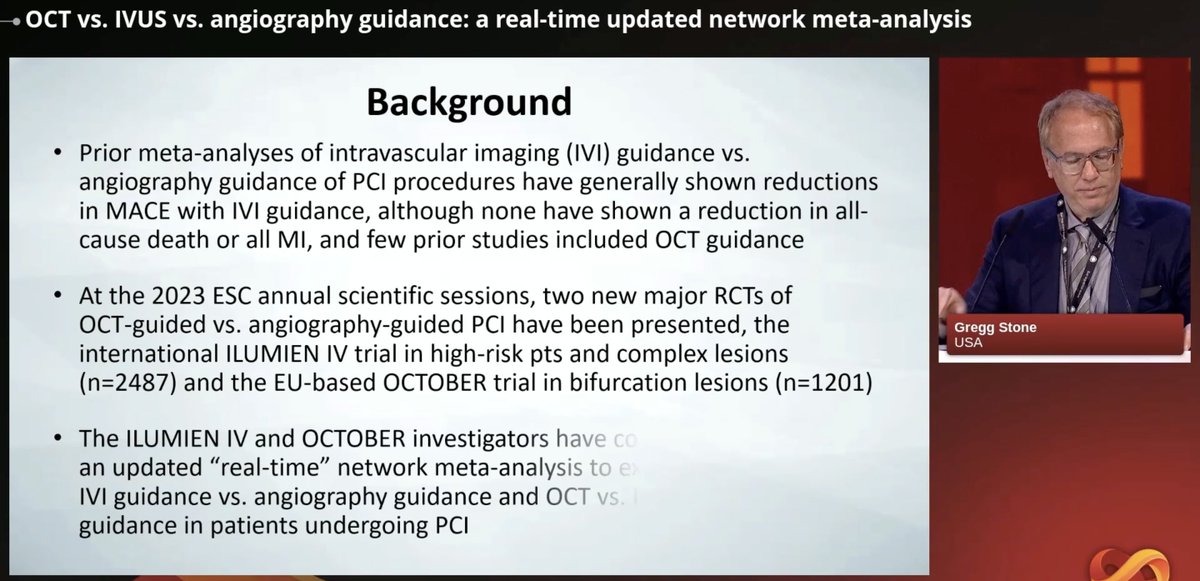

Great #AHA23 so far: AHA Research 🥸8 Trials: 8 take aways below Read the read👇👇 1/ATRESIA: Patients with subclinical atrial fibrillation can benefit from apixaban to reduce the risk of stroke and systemic thromboembolism.